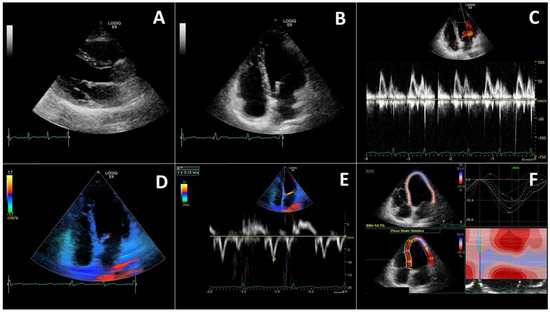

- Szekely, Y.; Lichter, Y.; Taieb, P.; Banai, A.; Hochstadt, A.; Merdler, I.; Gal Oz, A.; Rothschild, E.; Baruch, G.; Peri, Y.; et al. Spectrum of Cardiac Manifestations in COVID-19: A Systematic Echocardiographic Study. Circulation 2020, 142, 342–353. [Google Scholar] [CrossRef]

- Dweck, M.R.; Bularga, A.; Hahn, R.T.; Bing, R.; Lee, K.K.; Chapman, A.R.; White, A.; Di Salvo, G.; Sade, L.E.; Pearce, K.; et al. Global evaluation of echocardiography in patients with COVID-19. Eur. Heart J. Cardiovasc. Imaging 2020, 21, 949–958. [Google Scholar] [CrossRef]

- Barman, H.A.; Atici, A.; Tekin, E.A.; Baycan, O.F.; Alici, G.; Meric, B.K.; Sit, O.; Genc, O.; Er, F.; Gungor, B.; et al. Echocardiographic features of patients with COVID-19 infection: A cross-sectional study. Int. J. Cardiovasc. Imaging 2021, 37, 825–834. [Google Scholar] [CrossRef]

- Deng, Q.; Hu, B.; Zhang, Y.; Wang, H.; Zhou, X.; Hu, W.; Cheng, Y.; Yan, J.; Ping, H.; Zhou, Q. Suspected myocardial injury in patients with COVID-19: Evidence from front-line clinical observation in Wuhan, China. Int. J. Cardiol. 2020, 311, 116–121. [Google Scholar] [CrossRef]

- Li, Y.; Li, H.; Zhu, S.; Xie, Y.; Wang, B.; He, L.; Zhang, D.; Zhang, Y.; Yuan, H.; Wu, C.; et al. Prognostic Value of Right Ventricular Longitudinal Strain in Patients With COVID-19. JACC Cardiovasc. Imaging 2020, 13, 2287–2299. [Google Scholar] [CrossRef] [PubMed]

- Lazzeri, C.; Bonizzoli, M.; Batacchi, S.; Peris, A. Echocardiographic assessment of the right ventricle in COVID -related acute respiratory syndrome. Intern. Emerg. Med. 2021, 16, 1–5. [Google Scholar] [CrossRef] [PubMed]

- D’Alto, M.; Marra, A.M.; Severino, S.; Salzano, A.; Romeo, E.; De Rosa, R.; Stagnaro, F.M.; Pagnano, G.; Verde, R.; Murino, P.; et al. Right ventricular-arterial uncoupling independently predicts survival in COVID-19 ARDS. Crit. Care 2020, 24, 670. [Google Scholar] [CrossRef]

- Xie, Y.; Wang, L.; Li, M.; Li, H.; Zhu, S.; Wang, B.; He, L.; Zhang, D.; Zhang, Y.; Yuan, H.; et al. Biventricular Longitudinal Strain Predict Mortality in COVID-19 Patients. Front. Cardiovasc. Med. 2021, 7, 418. [Google Scholar] [CrossRef]

- Ozer, P.K.; Govdeli, E.A.; Baykiz, D.; Karaayvaz, E.B.; Medetalibeyoglu, A.; Catma, Y.; Elitok, A.; Cagatay, A.; Umman, B.; Oncul, A.; et al. Impairment of right ventricular longitudinal strain associated with severity of pneumonia in patients recovered from COVID-19. Int. J. Cardiovasc. Imaging 2021. [Google Scholar] [CrossRef] [PubMed]

- Gibson, L.E.; Di Fenza, R.; Lang, M.; Capriles, M.I.; Li, M.D.; Kalpathy-Cramer, J.; Little, B.P.; Arora, P.; Mueller, A.L.; Ichinose, F.; et al. Right Ventricular Strain Is Common in Intubated COVID-19 Patients and Does Not Reflect Severity of Respiratory Illness. J. Intensive Care Med. 2021, 36, 900–909. [Google Scholar] [CrossRef]

- Wibowo, A.; Pranata, R.; Astuti, A.; Tiksnadi, B.B.; Martanto, E.; Martha, J.W.; Purnomowati, A.; Akbar, M.R. Left and right ventricular longitudinal strains are associated with poor outcome in COVID-19: A systematic review and meta-analysis. J. Intensive Care 2021, 9, 9. [Google Scholar] [CrossRef]